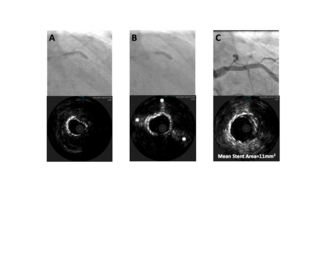

"There has been a sort of dogma that in very long lesions it is better to do atherectomy," says Ziad A. Ali, MD, DPhil, "but with the C2+, that thinking should no longer be relevant, because we now have 120 pulses to treat the whole vessel."...